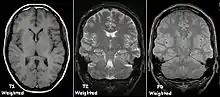

Examples of T1-weighted, T2-weighted and PD-weighted MRI scans

Each tissue returns to its equilibrium state after excitation by the independent relaxation processes of T1 (spin-lattice; that is, magnetization in the same direction as the static magnetic field) and T2 (spin-spin; transverse to the static magnetic field). To create a T1-weighted image, magnetization is allowed to recover before measuring the MR signal by changing the repetition time (TR). This image weighting is useful for assessing the cerebral cortex, identifying fatty tissue, characterizing focal liver lesions, and in general, obtaining morphological information, as well as for post-contrast imaging. To create a T2-weighted image, magnetization is allowed to decay before measuring the MR signal by changing the echo time (TE). This image weighting is useful for detecting edema and inflammation, revealing white matter lesions, and assessing zonal anatomy in the prostate and uterus.

The standard display of MRI images is to represent fluid characteristics in black and white images, where different tissues turn out as follows: